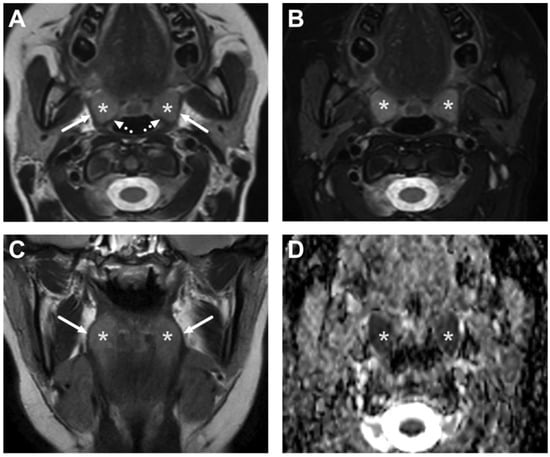

4.2. Retropharyngeal Abscesses and Suppurative Lymphadenitis